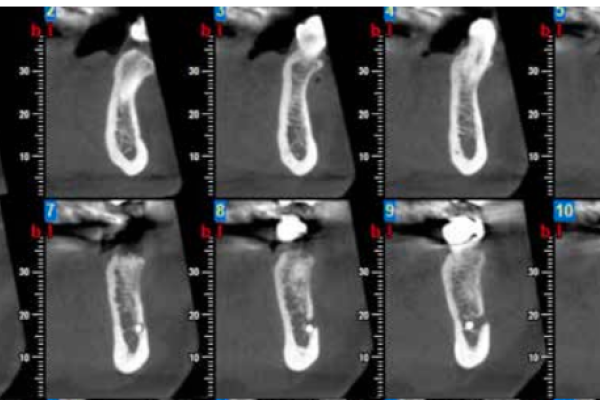

2 | ORIGINAL ARTICLE | RADIOGRAPHIC DIAGNOSIS OF IMPACTED MAXILLARY CANINES: COMPARISON BETWEEN TWO AND THREE DIMENSIONS |